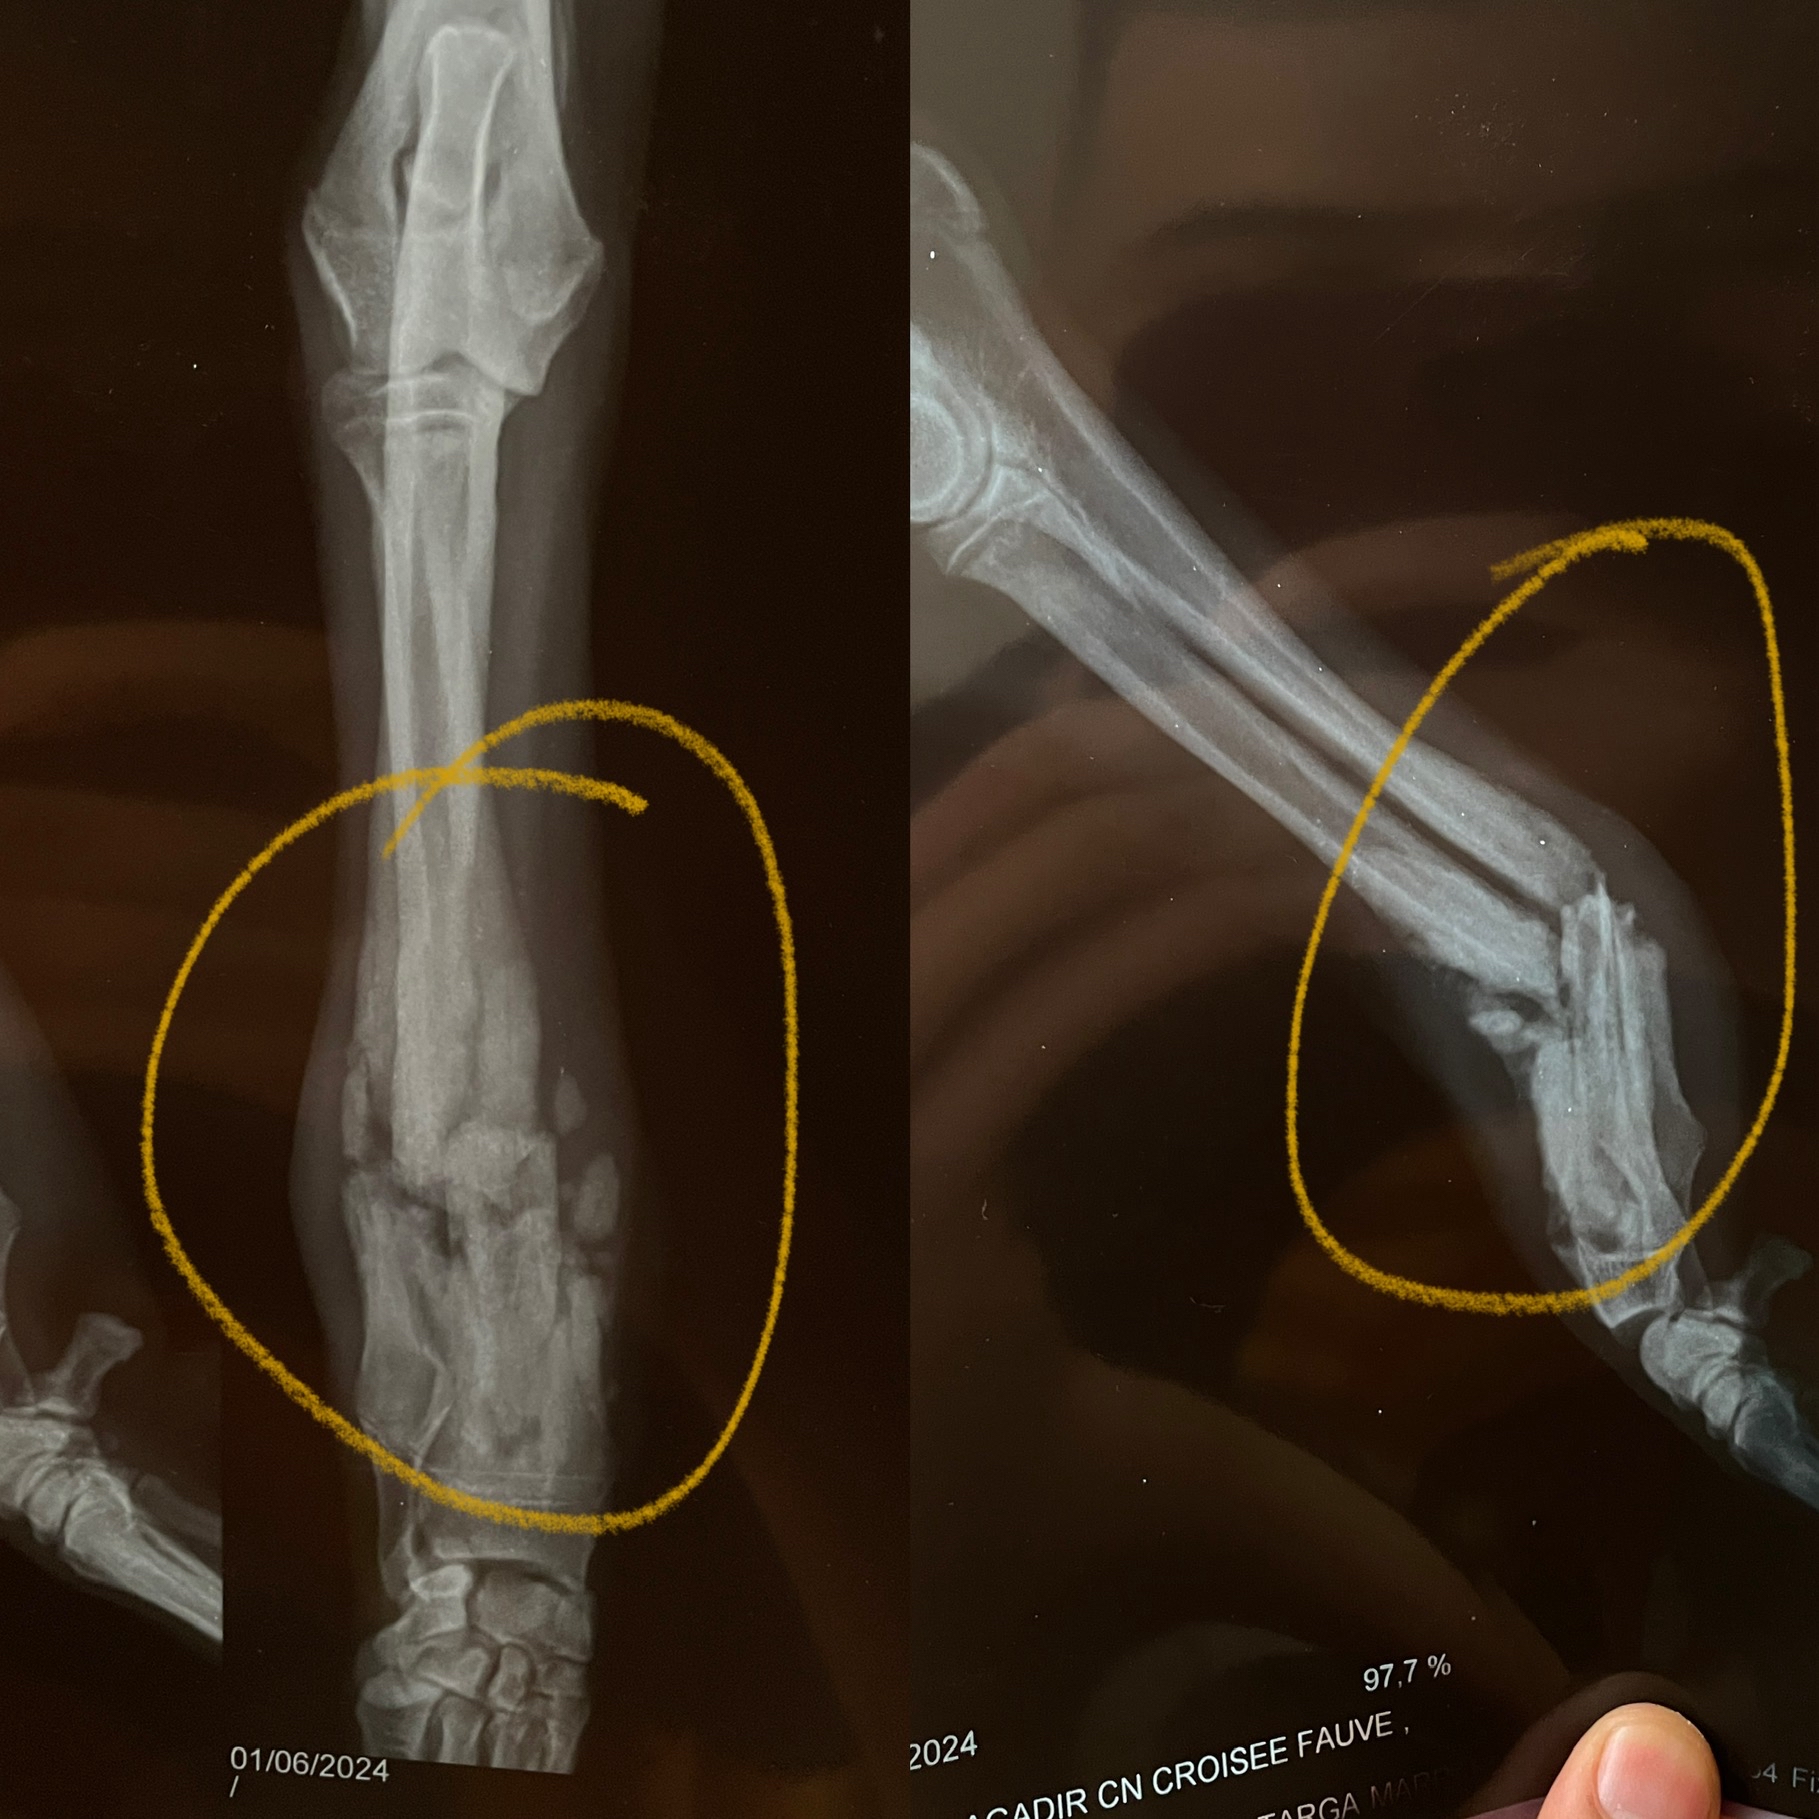

Wir haben voller Hoffnung gewartet mit der Publikation glaubten aber fast nicht daran! Beni wurde verunfallt in Bensergao Marokko gefunden mehr tot als lebendig. Die Vorderbeine waren ganz offensichtlich gebrochen und da sie die Hinterbeine nicht bewegte war das Rückgrat sicher auch beschädigt. Trotzdem zeigte sie ganz kleine Bewegungen und der Schwanz wedelte ebenfalls ganz leicht. Vorsichtig wurde sie geborgen und auf die Ferme gebracht. Dort zeigte sie ganz klar ihre Lebensfreude und den Willen, weiterleben zu wollen. Gestern wurde sie nun nach Marrakkesh gebracht und die Vorderbeine operiert. Drücken wir ihr ganz ganz fest die Daumen und Pfoten, dass auch ihr Rückgrat langsam wieder heilt und sie wieder laufen lernt. Helft ihr mit, die Kosten für sie zu tragen?